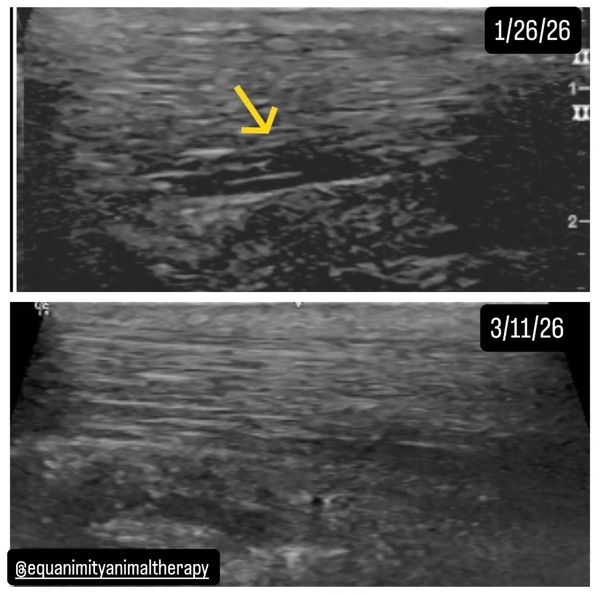

𝗗𝗶𝗮𝗴𝗻𝗼𝘀𝗶𝘀: LH medial 𝙨𝙪𝙨𝙥𝙚𝙣𝙨𝙤𝙧𝙮 𝙗𝙧𝙖𝙣𝙘𝙝 𝙩𝙚𝙖𝙧 with moderate synovitis of the tendon sheath. Inflammation of the digital tendon sheath causing impingement of the annular ligament.

Diagnosis obtained on January 26, 2026 via ultrasound. A rehabilitation program was made immediately following diagnosis that consisted of Acuscope treatment 4x a week with the vets hand walking protocol.

𝗥𝗲𝗰𝗵𝗲𝗰𝗸 appointment on March 11, 2026, roughly 𝟲 𝙬𝙚𝙚𝙠𝙨 after initial diagnostics were performed revealed that the medial suspensory branch tear was filling in substantially along with a big reduction in the synovial fluid. The tendon sheath inflammation is also substantially reduced. There was no heat or reluctance in movement that was present during the initial appointment. The owner was cleared to start introducing load bearing exercise (riding) again at a gradual incrementation to begin to strengthen the ligament.

Treatments will be continued at a reduced rate slowly tapering back but enough to support her while she is beginning to be ridden again to help prevent regression and to continue accelerating the production of linear fibers within the tear and keep reducing the tendon sheath inflammation. As a reminder, tendon and ligament tears fill with scar tissue so it is imperative to properly rehabilitate a soft tissue injury to ensure the scar tissue is as strong as possible to lower the chances of reinjury. Linear fibers = stronger, erratic fibers = weaker. It is imperative to teach the newly formed scar tissue to be as flexible as possible, which is why ridden work is slowly introduced again and in a certain formation. For example, no small circles that would put more weight on one side of the body versus the other, mainly straight lines in this phase.

To note, during the first recheck for a tendon or ligament injury the vet is generally checking to ensure the injury has not gotten worse, usually there is NO improvement at all let alone filling of the tear as what was accomplished in this case. This accelerated healing rate is what makes the Acuscope and Myopulse therapy system so valuable.